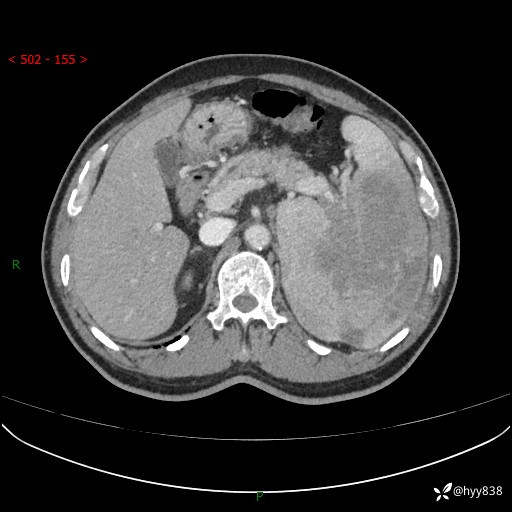

增强(动脉期+静脉期)